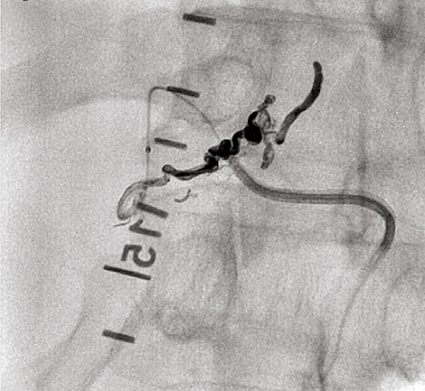

Undersökningen visade vidgade perimedullära kärl och ryggmärgsödem, fynd typiska för en spinal dural arteriovenös fistel med sekundär myelopati (Figur 3). På vårdavdelning i väntan på spinal angiografi och embolisering av fisteln försämrades patienten ytterligare och blev avföringsinkontinent. Akut spinal angiografi verifierade diagnosen, och man gjorde ett emboliseringsförsök som fick avbrytas på grund av svårigheter att nå bra kateterläge (Figur 4). Fisteln kunde slutas kirurgiskt senare samma dag.

Diagnostik. Den kliniska bilden och spinal MRT är helt avgörande för diagnosen. Okunnighet hos kliniker eller radiolog kan få som konsekvens att diagnosen ställs för sent eller inte alls, medan patienten utvecklar en obotlig parapares. De typiska fynden vid MRT är ödem och lätt svullnad av ryggmärgen torakolumbalt samt vidgade blodkärl (vener) dorsalt perimedullärt. Ödemet uppvisar hög signal centralt i ryggmärgen på T2-viktade bilder. De vida perimedullära venerna syns i cerebrospinalvätskan som slingriga strukturer med låg signal på T2-viktade bilder och hög signal på T1-viktade bilder efter intravenös kontrastmedelstillförsel.